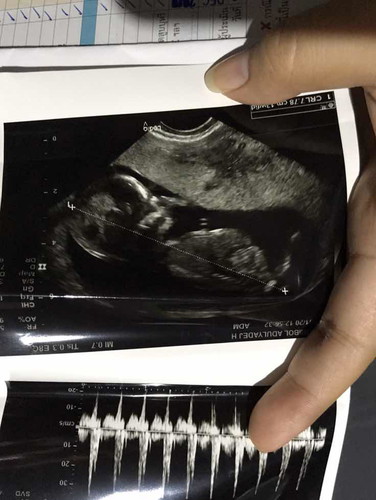

อัลตร้าซาว

แบบนี้หัวใหญ่ไปมั้ยคะหรือปกติ ซาวตอน14w อยากเห็นรูปซาวแม่ๆท่านอื่นบ้างค่ะ

ช่วงนี้ หัวจะโตค่า ยังไม่เข้ารูป ยังพัฒนาอีกค่า น่าจะปรกตินะคะ

ถ้าหมอไม่ได้ทักท้วงเรื่องกะโหลกศรีษะก็ไม่ต้องกังวลจ๊ะ